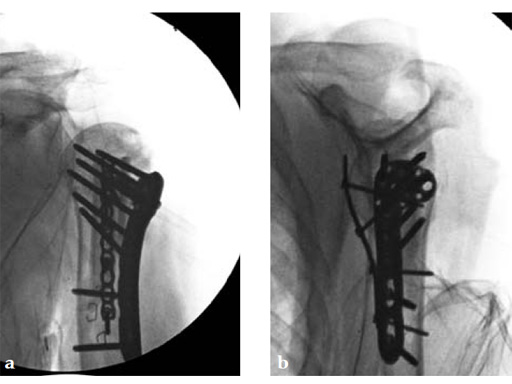

A 72-year-old woman suffered a four-part fracture of the left proximal humerus following a fall from a standing height. The patient underwent open reduction and internal fixation of the proximal humeral fracture.